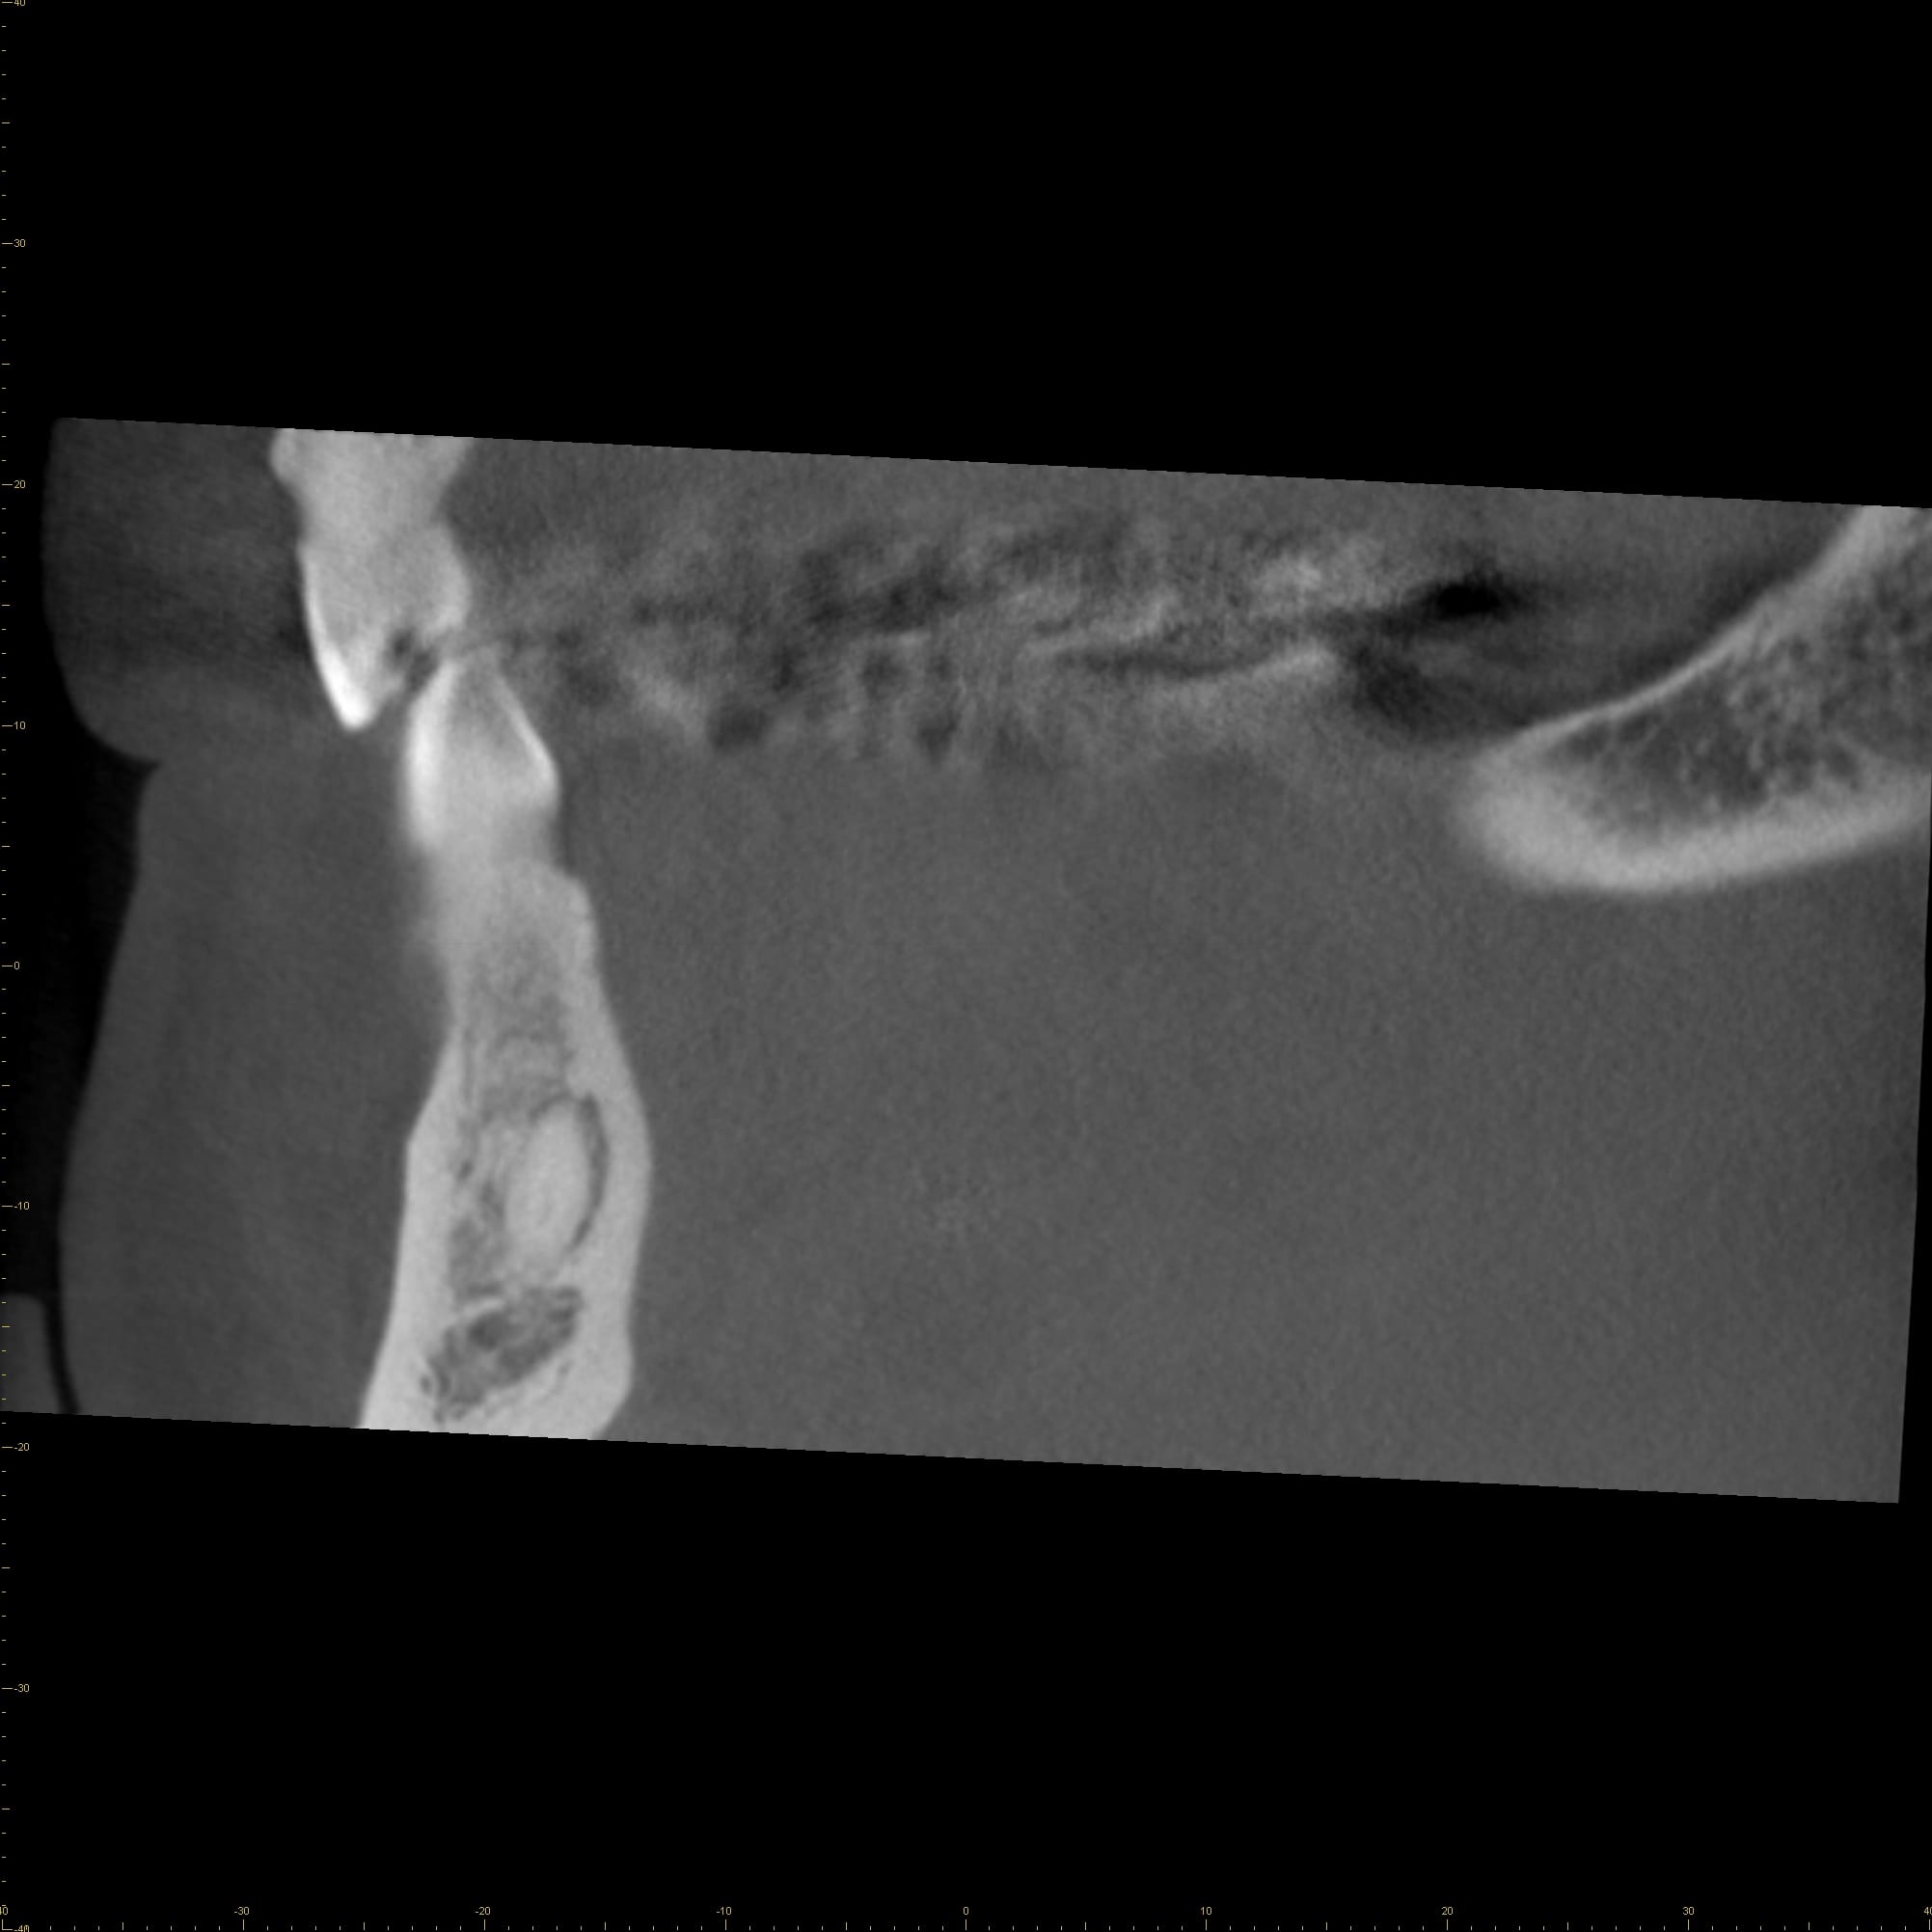

From www.morita.com

Cone beam computed tomography in dentistry MORITA What Is Coronal Remnants As a result, the extraction of these remnants would need to be performed to remove what is left of the child’s baby tooth. Developed by the ada, this guide is published to educate dentists and others in the dental. Full coronal restoration of primary incisors may be indicated for a number of reasons. A primary tooth with no roots remaining. What Is Coronal Remnants.